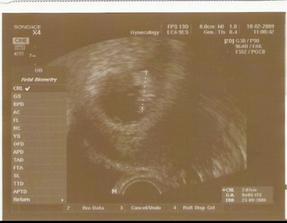

14.5. velký genetický uzv dopadl v pořádku - máme vše co máme mít a máme to tam kde to máme mít... Jinak maminka cítí krásně moje pohyby a dokonce už si v pondělí (25.5.) všimla, že když kopu hodně, tak už je to vidět i na hýbání bříška...